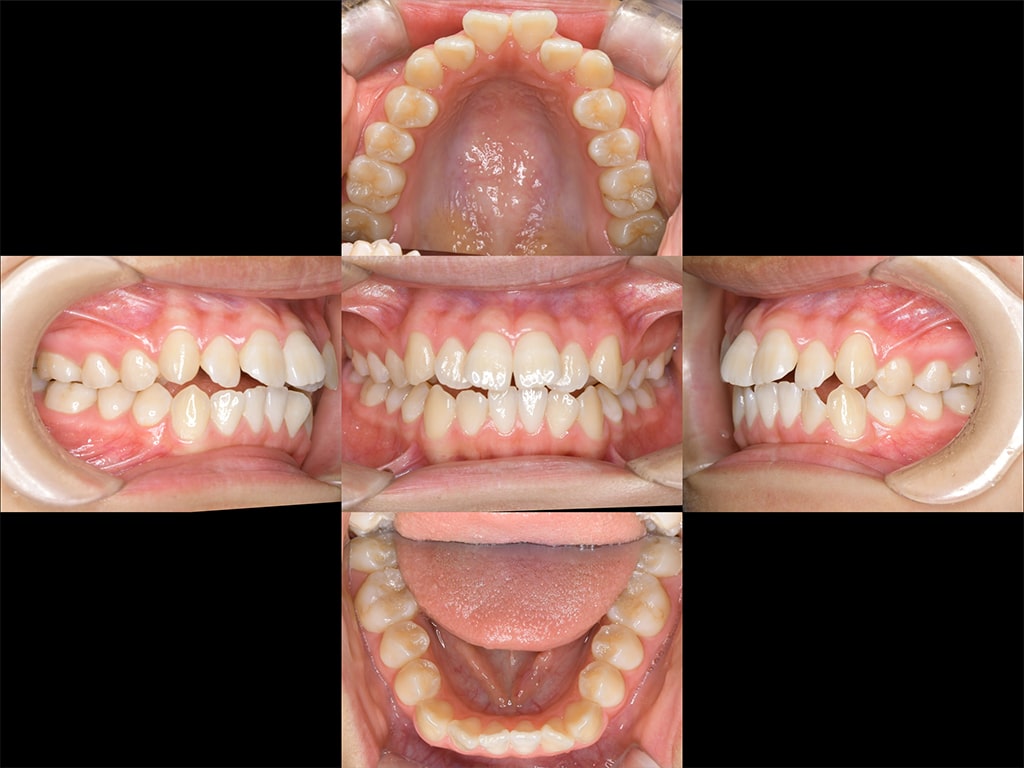

Before

After

| 年齢 | 13歳 女性 |

|---|---|

| 治療方法 | 矯正治療 インビザライン ホームホワイトニング |

| 治療期間 | 1年6ヶ月 |

| 治療費用 | 880,000円(税込) |